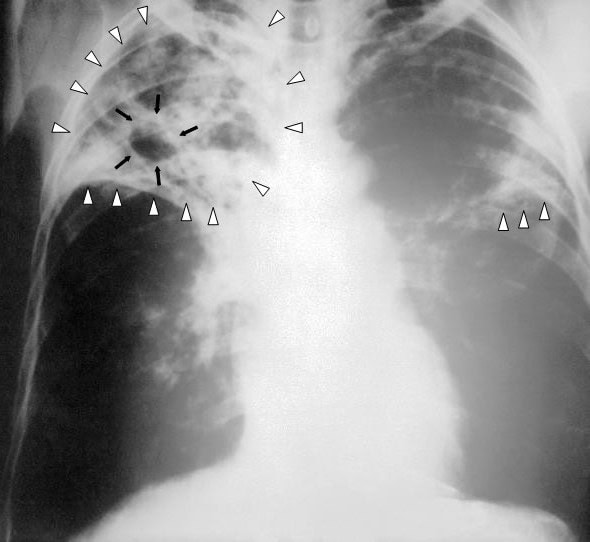

שחפת ריאתית נגרמת על ידי החיידק Mycobacterium tuberculosis והיא מועברת בעיקר דרך האוויר באמצעות טיפות זעירות שמשתחררות בעת שיעול או עיטוש של אדם נגוע. עם זאת, במקרה של פעוטות, סיכון ההדבקה לאחרים נחשב נמוך יחסית, מאחר והם אינם משתעלים בעוצמה המספיקה להפצת החיידק.

שחפת הייתה בעבר אחת המחלות הקטלניות ביותר בעולם, אך עם התקדמות הרפואה, הפכה למחלה בת-טיפול באמצעות אנטיביוטיקה ייעודית הניתנת למשך מספר חודשים. עם זאת, שחפת שאינה מטופלת עלולה להחמיר ולגרום לנזקים חמורים לריאות ואף לסכן חיים.